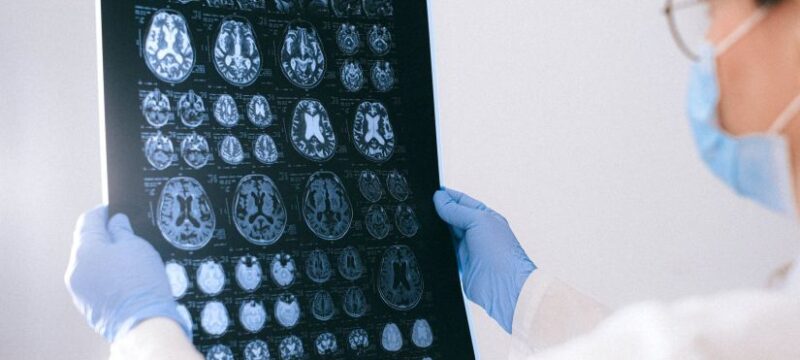

ΗΠΑ: Περίεργα περιστατικά λοιμώξεων στον εγκέφαλο των παιδιών

Τα Κέντρα Ελέγχου και Πρόληψης Νοσημάτων των ΗΠΑ διερευνούν μια σειρά από περίεργα περιστατικά που έχουν να κάνουν με τη δημιουργία κύστεων στον εγκέφαλο των παιδιών στο Λας Βέγκας και στη Νεβάδα ενώ γιατροί κάνουν λόγο για αύξηση των κρουσμάτων… Το 2022, ο αριθμός των περιστατικών τριπλασιάστηκε στη Νεβάδα, αυξάνοντάς τα από τέσσερα και πέντε […]